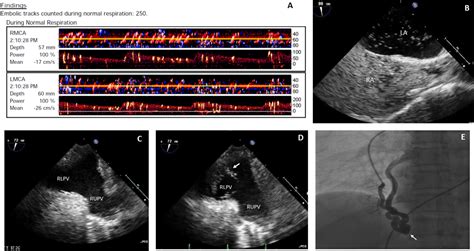

• Echocardiogram: This is a non-invasive test that uses sound waves to create images of the heart. A transesophageal echocardiogram (TEE) is often used to get a clearer view of the heart's structures.

• Bubble Study: During an echocardiogram, a saline solution with microbubbles is injected into a vein. If the bubbles appear in the left atrium, it indicates the presence of a PFO.

• MRI: Magnetic resonance imaging can also be used to visualize the heart and detect a PFO.

• CT Scan: A computed tomography scan can provide detailed images of the heart and help identify a PFO.